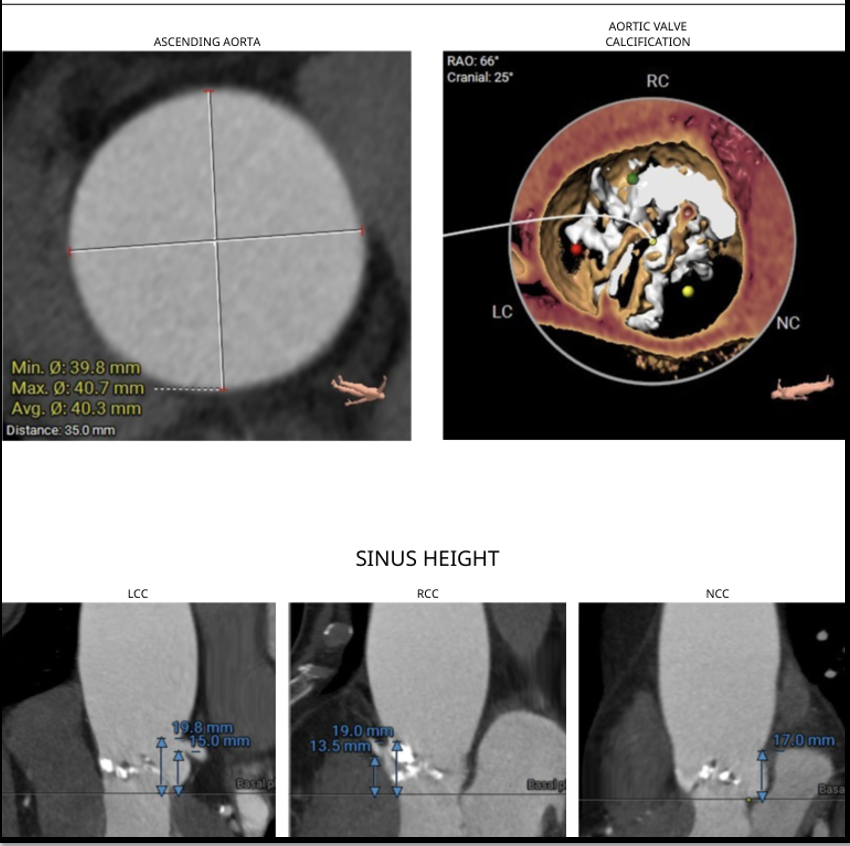

ECG revealed features of left ventricular hypertrophy. 2D echocardiography showed preserved left ventricular ejection fraction with severe calcific aortic stenosis, CT-TAVI protocol revealed Type 1 bicuspid aortic valve (R-L fusion), dilated ascending aorta, a perimeter-derived annulus of 22.2 mm (average 22 mm), sinus of Valsalva diameters RCC 29 mm, LCC 30.7 mm, NCC 32 mm, LVOT perimeter 22 mm, significant valve calcification, steep LVOT angle (68¡Æ), and well-sized, non-tortuous femoral access